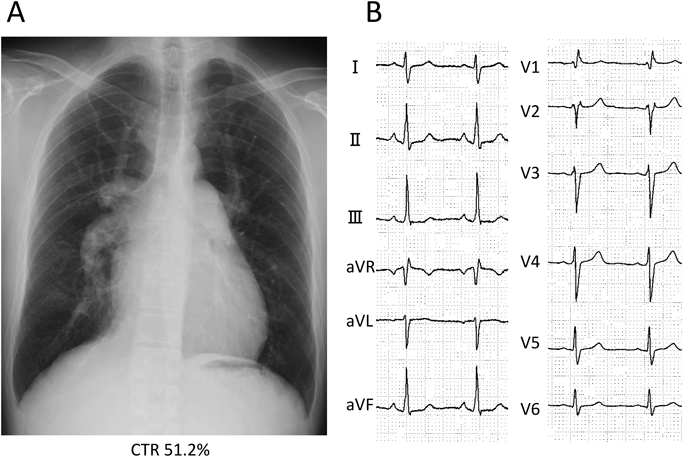

A 42-year-old man was referred to our hospital because of fatigue and exertional dyspnea; he often complained dyspnea when going up stairs. The cause of fatigue and dyspnea had not been detected, although he visited multiple clinics and his chest radiography at medical checkup already showed dilatation of the bilateral pulmonary arteries (Fig. 1A). He was unable to go to work due to his symptoms. On physical examination, his blood pressure and pulse rate were 114/86 mmHg and 78 bpm, respectively. He had a regular rhythm and a respiratory rate of 12 bpm with a percutaneous oxygen saturation of 98% in room air. His second heart sound was accentuated, and no heart murmur audible. A 6-minute walk distance was 390 m. These findings suggested that he was classified into New York Heart Association (NYHA) functional class III. Electrocardiography showed regular sinus rhythm, axis deviation and right ventricular hypertrophy with complete right bundle branch block (Fig. 1B). Echocardiography showed enlargement of the right ventricle and flattening of the interventricular septum. Doppler measurement of tricuspid regurgitation revealed that estimated right ventricular pressure was 103.1 mmHg (Fig. 2A, B). Contrast-enhanced computed tomography illustrated that the right upper and middle pulmonary veins (PVs) drained into the SVC, and that the pulmonary arteries as well as the right ventricle were dilated. Additionally, these anomalous PVs had been shifted upward due to the dilated right pulmonary artery (Fig. 3). During this investigation, the patient suddenly collapsed with low blood pressure, and immediate cardiopulmonary resuscitation was needed. Probably, PAH deteriorated subsequent to injection of contrast media, causing acute volume overload and an increase in pulmonary vascular resistance. Right heart catheterization (RHC) eventually revealed the systemic to pulmonary blood flow ratio (Qp/Qs) 1.4, mean pulmonary arterial pressure (PAP) 91 mmHg, pulmonary capillary wedge pressure 12 mmHg, and pulmonary vascular resistance (PVR) 20.3 WU, respectively (Table 1). Acute vasodilator test using the combination of inhaled oxygen and nitric oxide (iNO) showed PAP and PVR remaining unchanged. PAH related with heredity, drugs and left ventricular dysfunction, respiratory diseases were ruled out after PAH workup. Consequently, we started a combined therapy using PAH-specific drugs. Macitentan (20 mg/day) and tadalafil (10 mg/day) were immediately administered after the RHC. In addition, selexipag was gradually increased from 2 to 10 mg/day at our outpatient clinic. The second RHC took place 6 months after introduction of the PAH drugs, measuring mean PAP 49 mmHg (69/39 mmHg) and PVR 8.6 WU. The Qp/Qs ratio had increased to 2.0 (Table 1). The third RHC was carried out 9 months after initiation of the PAH drugs; mean PAP 45 mmHg (64/30 mmHg), which was similar to the value at the second RHC. Furthermore, PVR markedly improved (down to 2.7 WU), and the Qp/Qs ratio increased (up to 3.2) (Table 1). The patient’s exercise tolerance became better thereafter as his PAH improved. On the other hand, side effects of the PAH drugs, such as diarrhea and headache, gradually resulted in poor medication adherence. As interruption of PAH drugs likely results in progressive PAH, we decided to recommend surgical repair.

Fig. 2 Preoperative transthoracic echocardiogram

The short axis view shows left ventricular deformity due to right ventricular dilatation (A). Doppler measurement of tricuspid regurgitation indicates high right ventricular pressure (B). LV, left ventricle; RV, right ventricle.